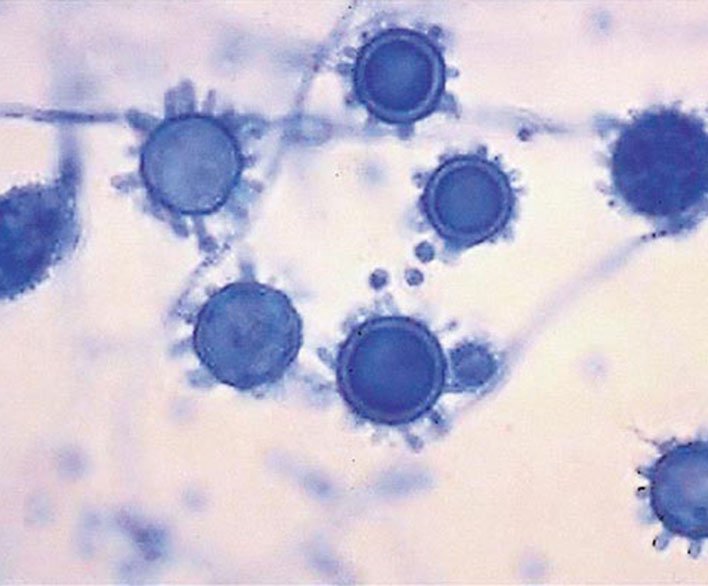

Valley fever is common name of deadly fungus Coccidioides immitis or Coccidioides posadasii.